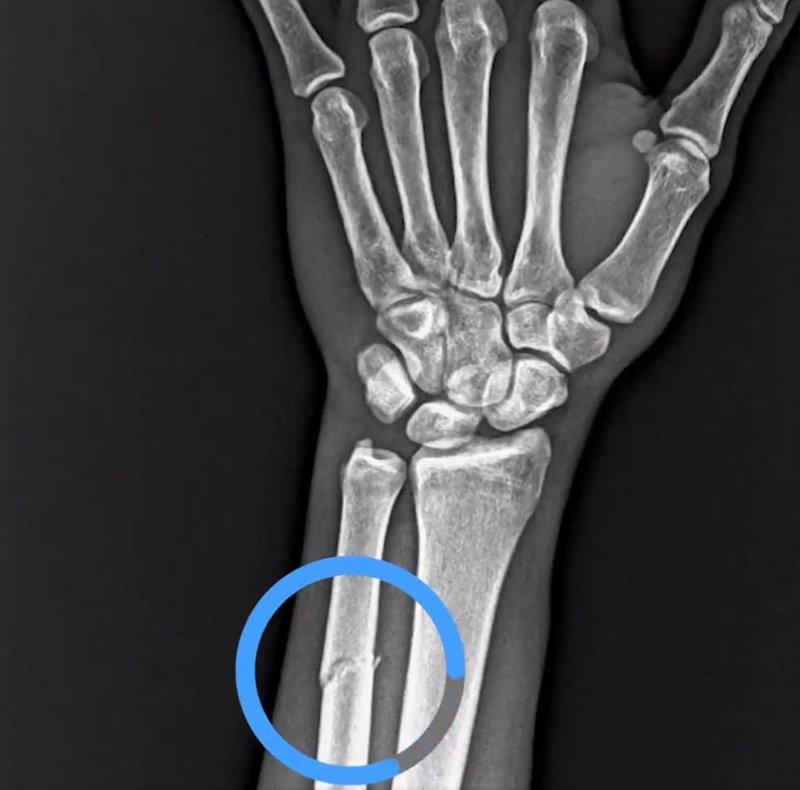

Ziraat Türkiye Kupası çeyrek final maçında Trabzonspor evinde RAMS Başakşehir'i 1-0 mağlup etti ve adını yarı finale yazdırdı. Bordo-mavili ekipte Paul Onuachu'nun karşılaşmada kolundan sakatlandı. Çekilen MR'a göre yıldız oyuncunun kolunda kırık tespit edildi. Trabzonspor, resmi sosyal hesabından yaptığı paylaşımda tepkisini ifade etti.

VAR'da göremediğiniz pozisyonun röntgen görüntüsü⁰#AdaletinizBatsın pic.twitter.com/DwFUeeSXLf